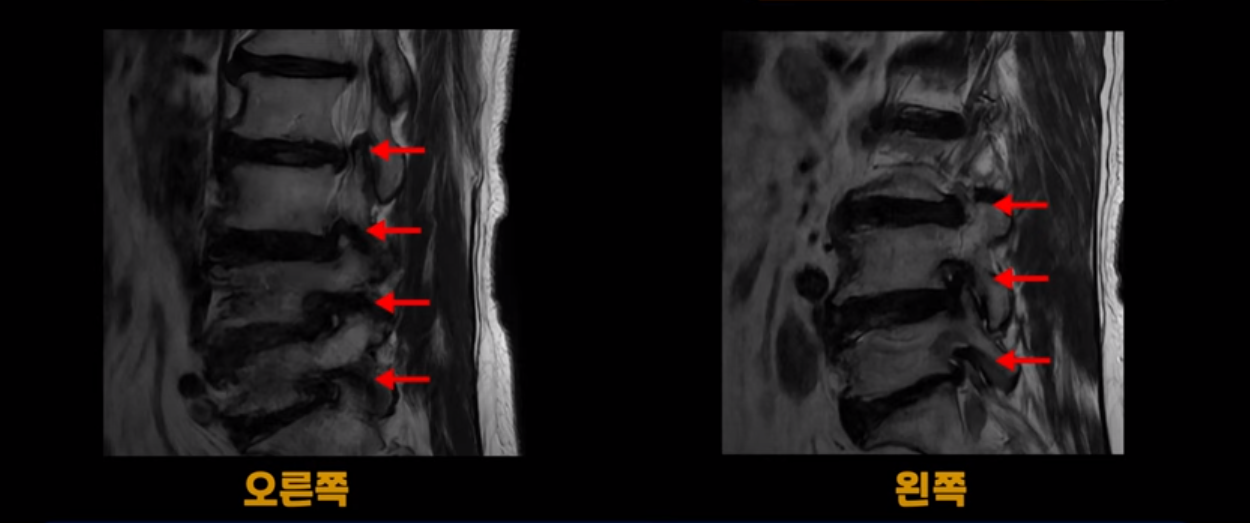

이 환자분은 MRI로 보면 허리 여러 마디가 신경이 매우 심하게 눌려 보이는 분입니다. 이분 MRI를 보면서 간단히 설명해 드린 후 어떻게 이렇게 신경이 심하게 눌린 환자분이 수술 없이 근육신경재활치료로 좋아질 수 있는지, 다리가 아파 걷지 못하는 환자가 어떻게 안 아프고 잘 걸을 수 있게 되는지, 10년 동안 괴로웠던 양 발의 시린 증상은 어떻게 사라질 수 있는지, 치료는 어떻게 하는지 자세히 설명 드리겠습니다.

MRI 보시면 (2-8) 허리의 5마디가 전부 다 심하게 퇴행되어 있습니다.

5마디 전부 다 심한 중심성 협착이 있습니다.

이렇게 모두 다 심하게 막히는 경우는 드문데요. 또한 오른쪽, 왼쪽 신경이 빠져나가는 추간공도 다 심하게 막혀있습니다.

오른쪽, 왼쪽 이렇게 신경 구멍들이 다 좁아지고 신경이 눌리니까 양쪽 다리가 발바닥까지 아파서 걷기 어렵고 양쪽 발이 10년 넘게 시린 겁니다. 당연히 수술해서 눌린 신경을 풀어줘야 한다고 들으셨는데요. 이런 환자분을 어떻게 수술 없이 치료할까요? 지금부터 설명해 드립니다.

이분 신경이 눌리는 증상은 오래됐지만, 증상이 아주 심해진 건 올해 들어와서입니다. 그럼, 이분 MRI 영상도 이렇게 심하게 안 좋아진 게 올해 들어와서일까요? 이분의 MRI로 보이는 협착은 아주 오래된 겁니다. 그래서 신경 구멍이 심하게 좁아진 것도 올해가 아니고 오래된 겁니다. 작년, 재작년에 훨씬 덜 아팠을 때 MRI를 찍었어도 신경 구멍 좁은 정도는 별반 차이가 없었을 겁니다.